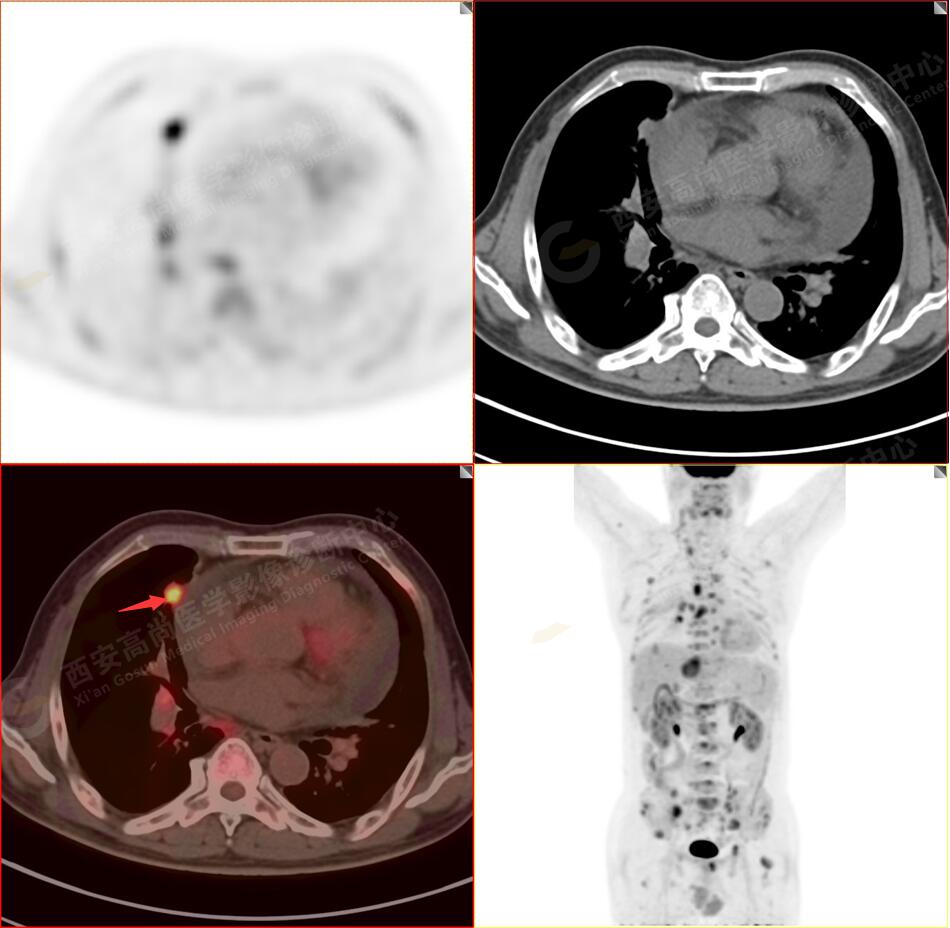

2.以下為全身多發(fā)轉移灶

2.雙肺內彌漫性分布大小不等實性小結節(jié)灶及粟粒狀高密度影,均未見FDG代謝明顯異常增高,均多考慮為癌性淋巴結炎及轉移性病變。

5.右側肱骨上段、左側肩胛骨、右側鎖骨胸骨端、胸骨、雙側多發(fā)肋骨、脊柱多發(fā)椎體及附件、雙側髂骨、雙側髖臼、雙側恥骨、雙側肱骨上段多發(fā)成骨性病變,呈不同程度FDG代謝異常增高,考慮為多發(fā)骨轉移瘤。